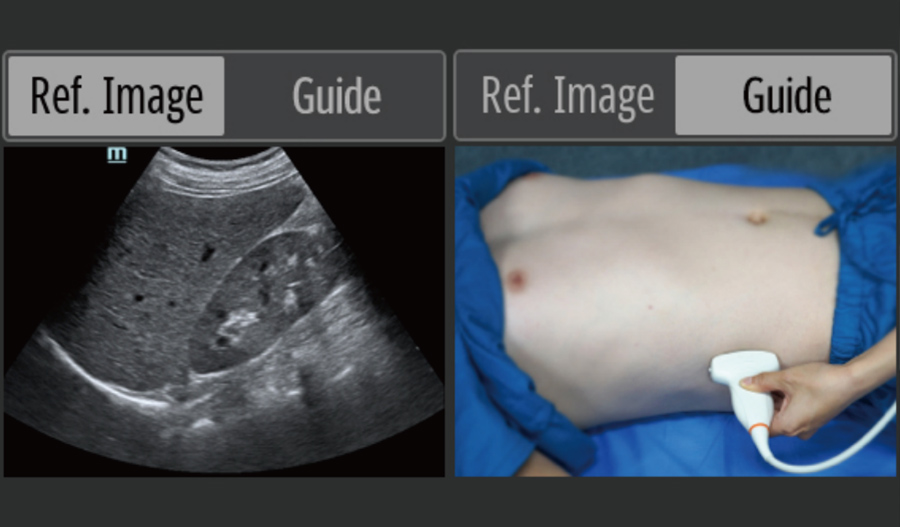

?chographie sur le lieu de soins (Point of Care ultrasound, POCUS)

Les fonctions ĂŠchographiques intĂŠgrĂŠes facilitent le diagnostic sur site et fournissent un guide dâutilisation intelligent pour une intuitivitĂŠ renforcĂŠe.

- RImages de rĂŠfĂŠrence & Guides dâutilisation

- Sonde phased array?: haute rĂŠsolution, largement utilisĂŠe